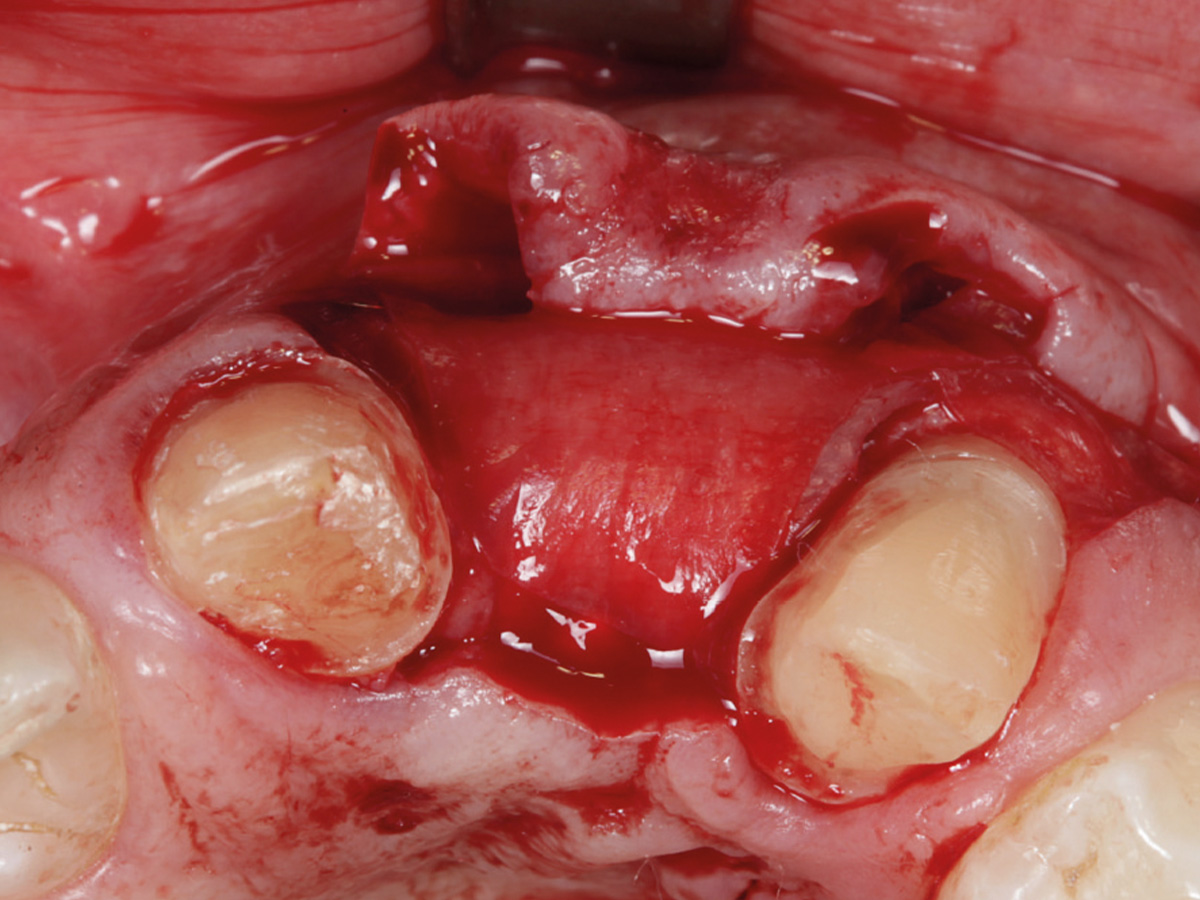

Abbildung 10

Regenerierter Bereich nach Lappenbildung. Gewebe gut durchblutet, Reste der Lamina sichtbar.